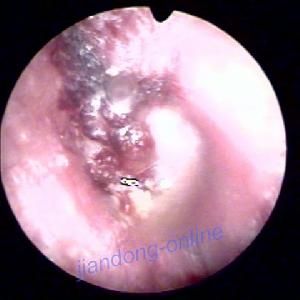

圖大庖性鼓膜炎或稱出血性大皰性鼓膜炎是伴隨感冒或流感的病毒性炎症,好發於兒童和青年人,主要表現為鼓膜及其鄰近外耳道皮膚出現充滿血清或血液皰疹,耳內劇痛。

2.外耳道深部皮膚及鼓膜充血和血皰形成。血皰破潰流出血性分泌物,鼓膜皰疹處表淺潰瘍或血痂。無鼓膜穿孔。

3.外耳道深部皮膚及鼓膜充血,並有血皰,呈紅褐色或紫紅色,血皰破潰,流出血性分泌物。培養無致病菌。